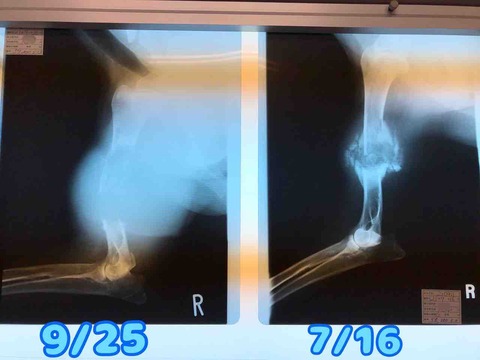

IMG_1073

骨折治療中だった脚が急にボコボコしてきたのが、6月(この写真は6/14)

この脚が…たったの2ヶ月で↓

FullSizeRender

ここまで大きくなり、腫瘍が破裂

IMG_1074

右前脚が骨折したのは6月21日

IMG_1066

たったの3ヶ月でこんなに大きくなってしまいました

骨肉腫が大きくなるスピード、めちゃくちゃ早い

最初は痛みがある前脚から断脚する予定でしたが、後ろ脚が先に破裂し始めてしまったので…

急遽後ろ脚から先に

この選択をして、正解でした

前脚を先に断脚してたら、回復前に後ろ脚がきっとダメになってしまって、手術を受けることが出来なかったと思います。